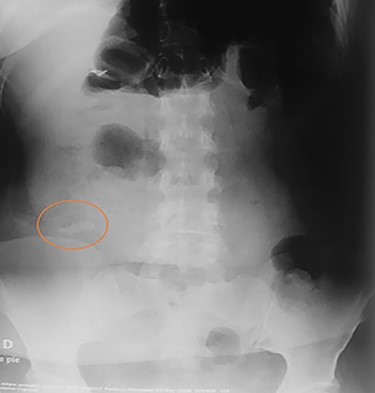

Abdominal CT, revealing two metal bodies, one in the stomach and one in the cecum.

On clinical examination, a dehydrated and tachycardic (112 bpm) patient was encountered, she had diffuse pain in her lower abdomen without tenderness. After reanimation, an abdominal X-ray found two metal bodies in the bowel (Fig. 1); therefore, a computed tomography (CT) was requested, which revealed two metal foreign bodies, (razor blades) one in the stomach and one in the cecum without pneumoperitoneum (Fig. 2). As the patient did not have any tenderness, an upper endoscopy and colonoscopy were planned. During the upper endoscopy, the razor blade was detected in the antrum and was embedded in the mucosa (Fig. 3). After several failed attempts to remove the foreign object, the procedure was interrupted due to a risk of inadvertent perforation, and surgery was decided.